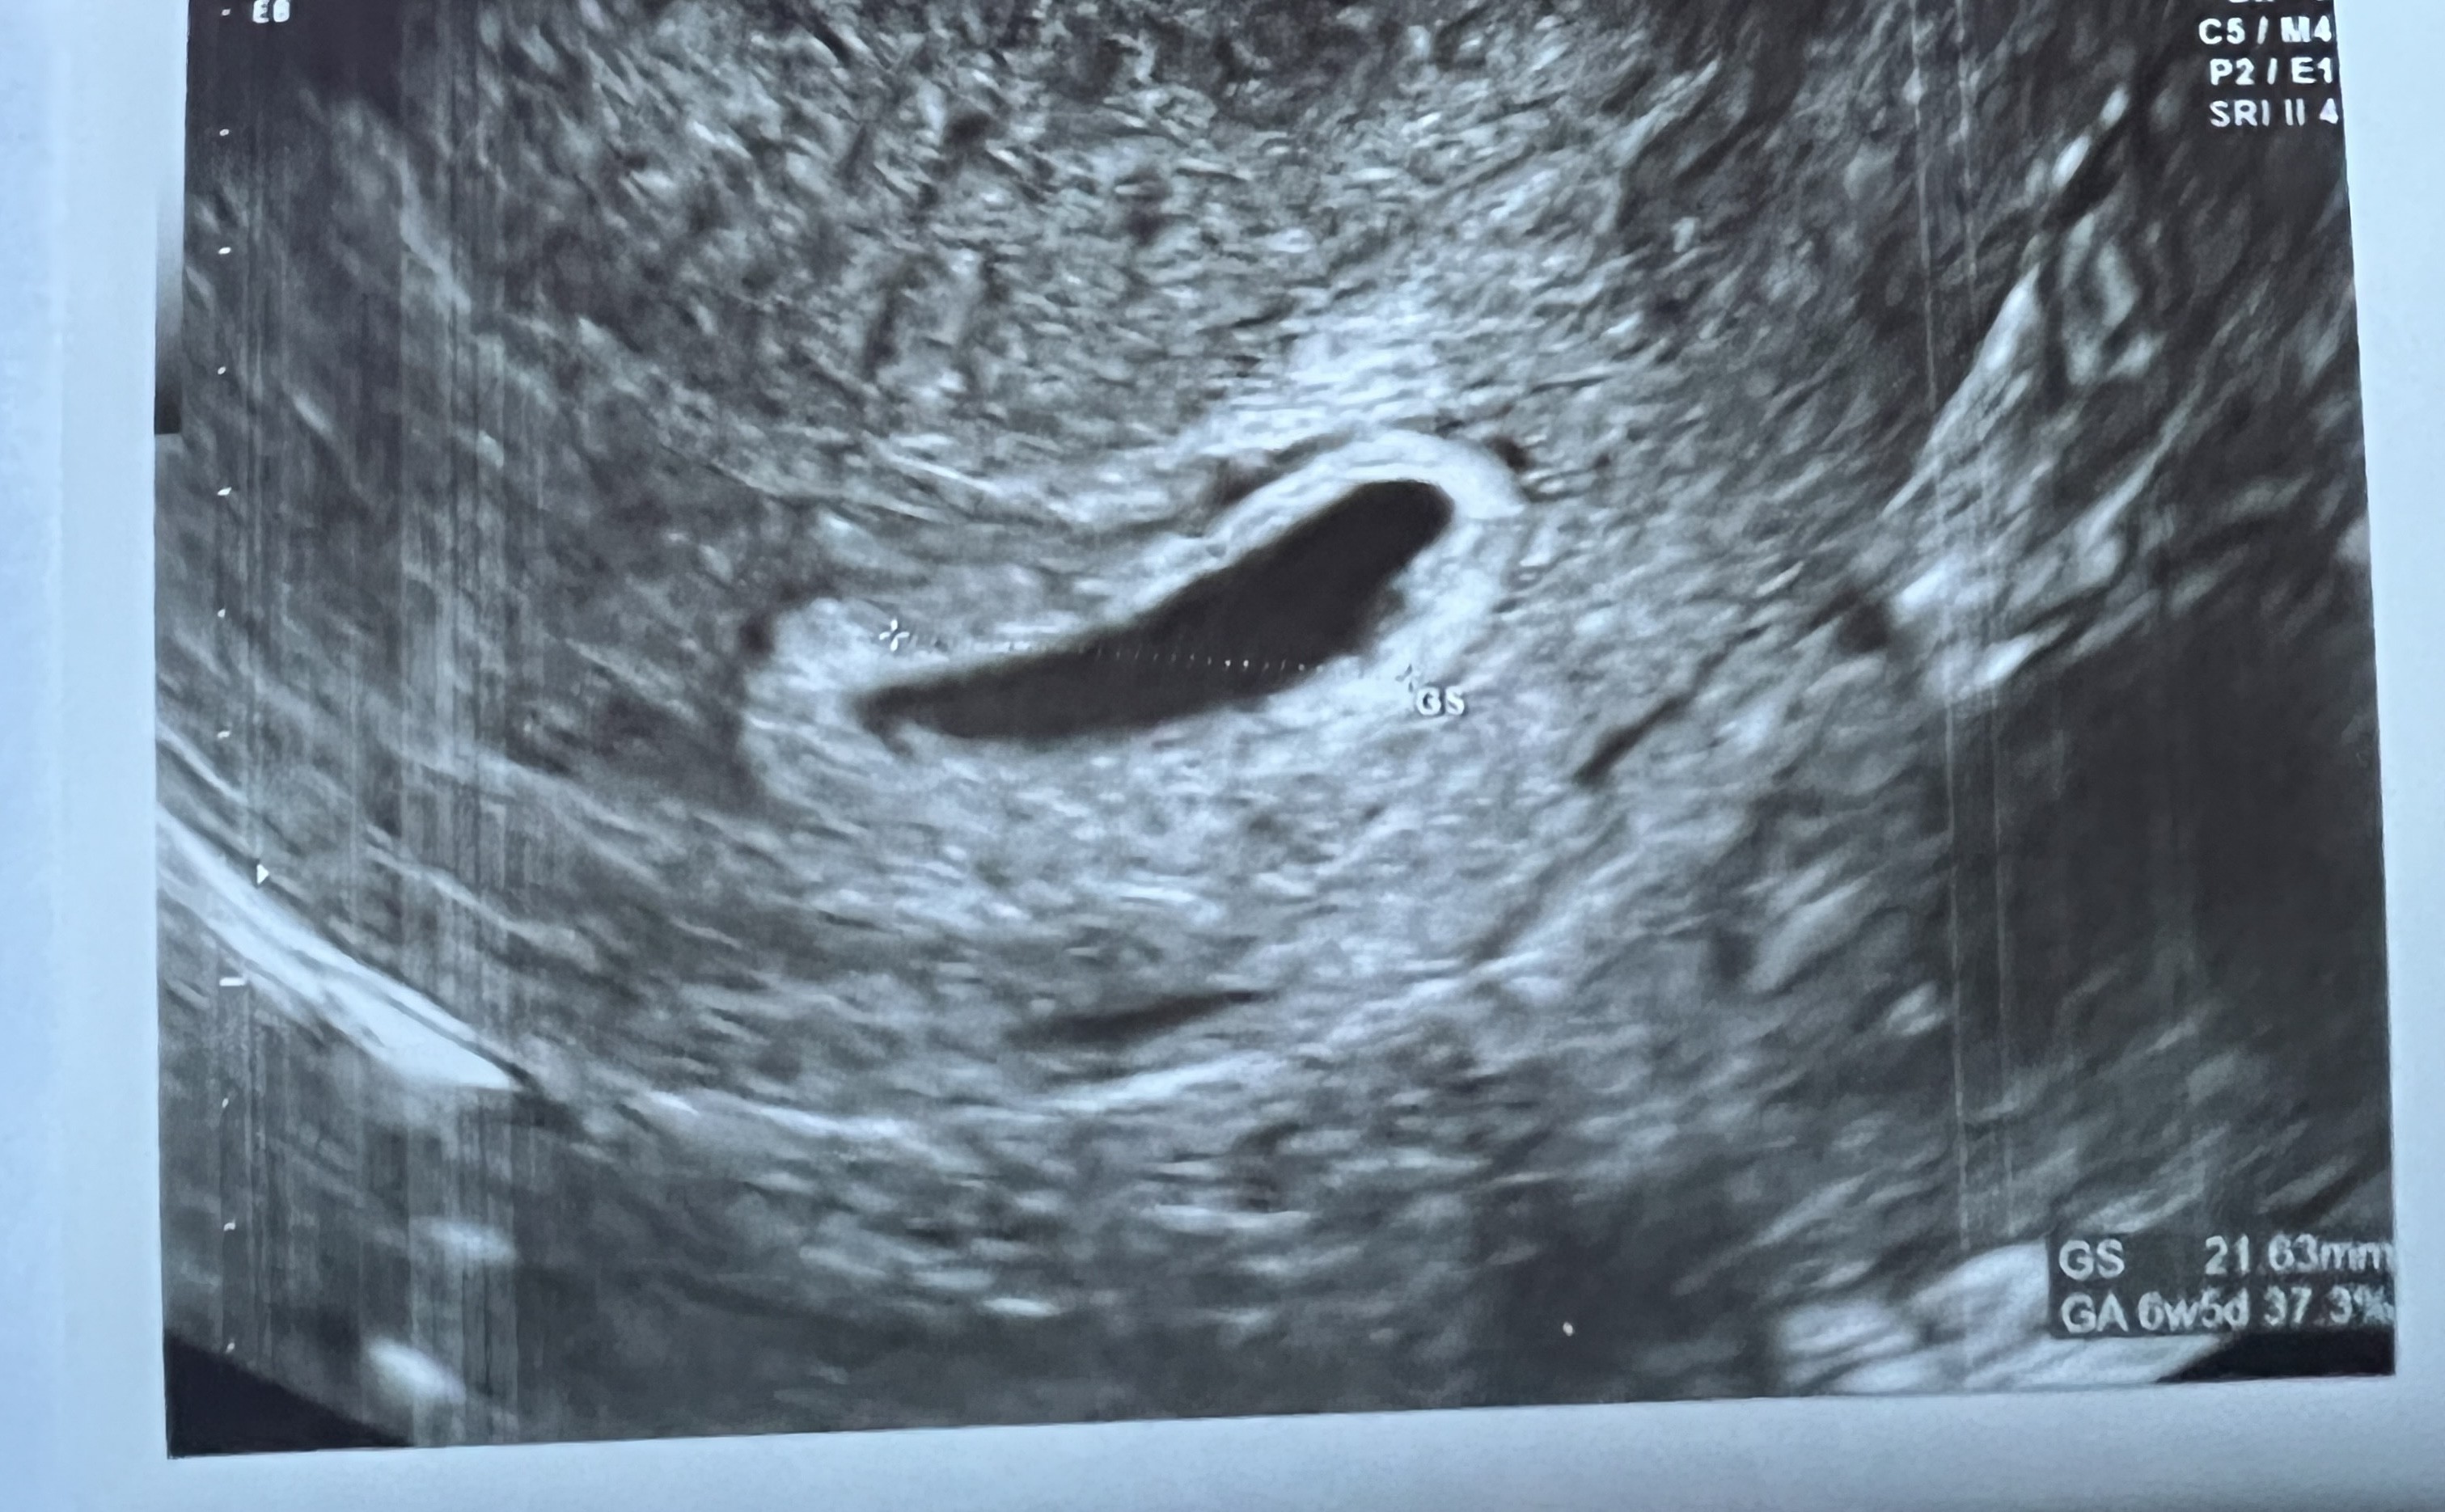

No lekarz generalnie ma większą wiedzęczy widziecie jakiekolwiek szanse? To mój 6w5d.

Lekarz przekreślił nadzieje i szanse, mam skierowanie do szpitala.